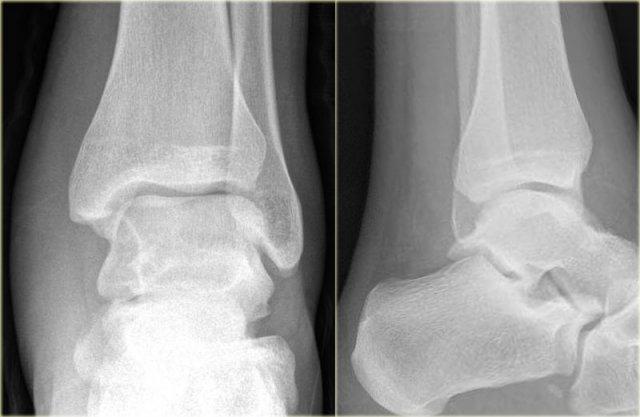

Các hình ảnh cho thấy một trường hợp gãy Weber B rõ ràng.

Trên tư thế thẳng (AP), đường thấu quang dạng tuyến tính là dấu hiệu gợi ý gãy tertius (mũi tên đỏ).

Dấu hiệu này xuất hiện do sự lệch trục nhẹ của mảnh gãy.

Tương tự, trong một số trường hợp, sự lệch trục có thể tạo ra một đường tăng tỷ trọng dạng tuyến tính.

Trong trường hợp này, có gãy Weber B kèm theo bong điểm bám mắt cá trong.

Đường tăng tỷ trọng trên tư thế thẳng (AP) gợi ý một mảnh gãy tertius lớn.

Gãy tertius này cũng có thể thấy trên tư thế nghiêng, nhưng trong nhiều trường hợp chúng ta cần kết hợp thông tin từ cả hai tư thế nghiêng và thẳng để chẩn đoán gãy tertius.